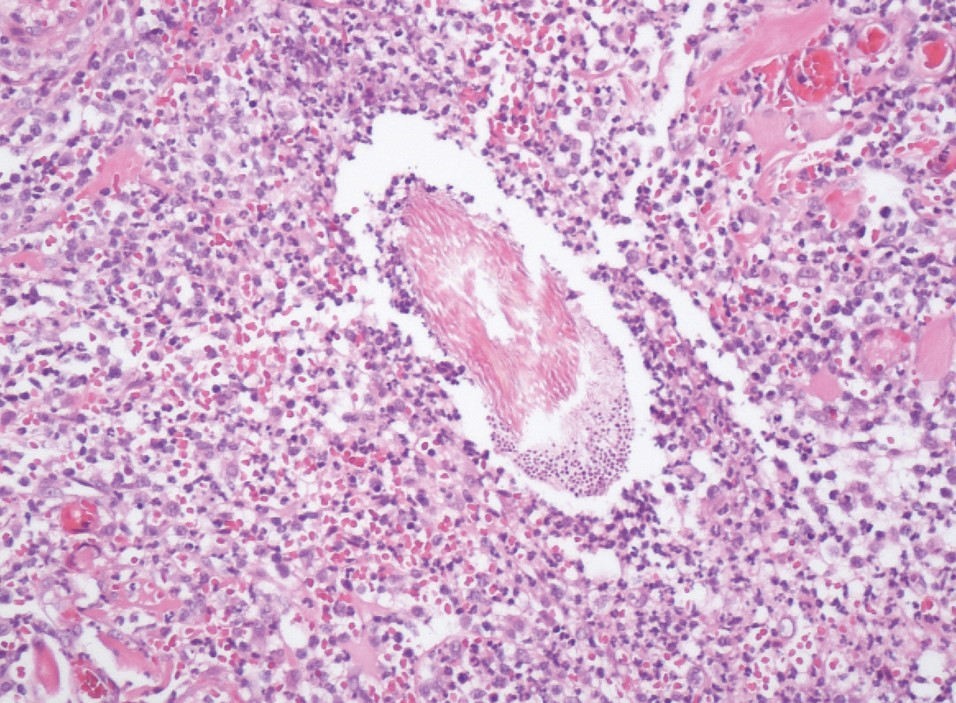

La biopsia del punch è stata prelevata dalla pelle nell’area periauricolare. L’esame istologico ha rivelato un’infiammazione grave, nodulare, piogranulomatosa e perifollicolare con foruncolosi multifocale. Elementi fungini (spore e ife) sono stati identificati nella sezione colorata di routine con ematossilina ed eosina (H&E). La loro presenza è stata confermata dalla colorazione Periodic acid-Schiff (PAS). I risultati istologici erano compatibili con un’infezione fungina superficiale della pelle – dermatofitosi (fig. 4A e B).

- Figura 4A: Dermatofitosi su cute con pelo di un cane: spore fungine e ife intorno ai fusti piliferi nei follicoli piliferi e foruncolosi; 20x, colorazione ematossilina e eosina (H&E) (A); 40x, colorazione Periodic acid–Schiff (PAS) (B)

- Figura 4B